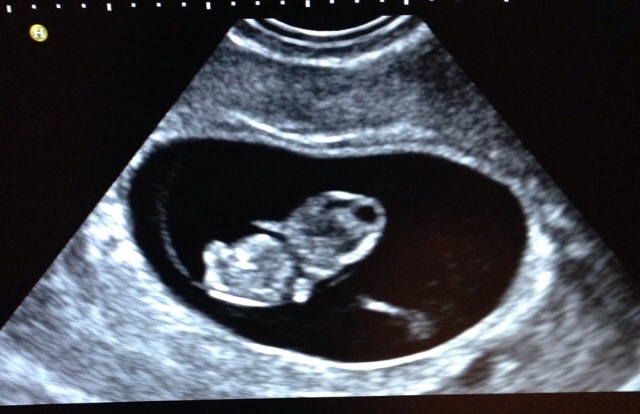

• Our sweet bean :) at 8 weeks 5 days